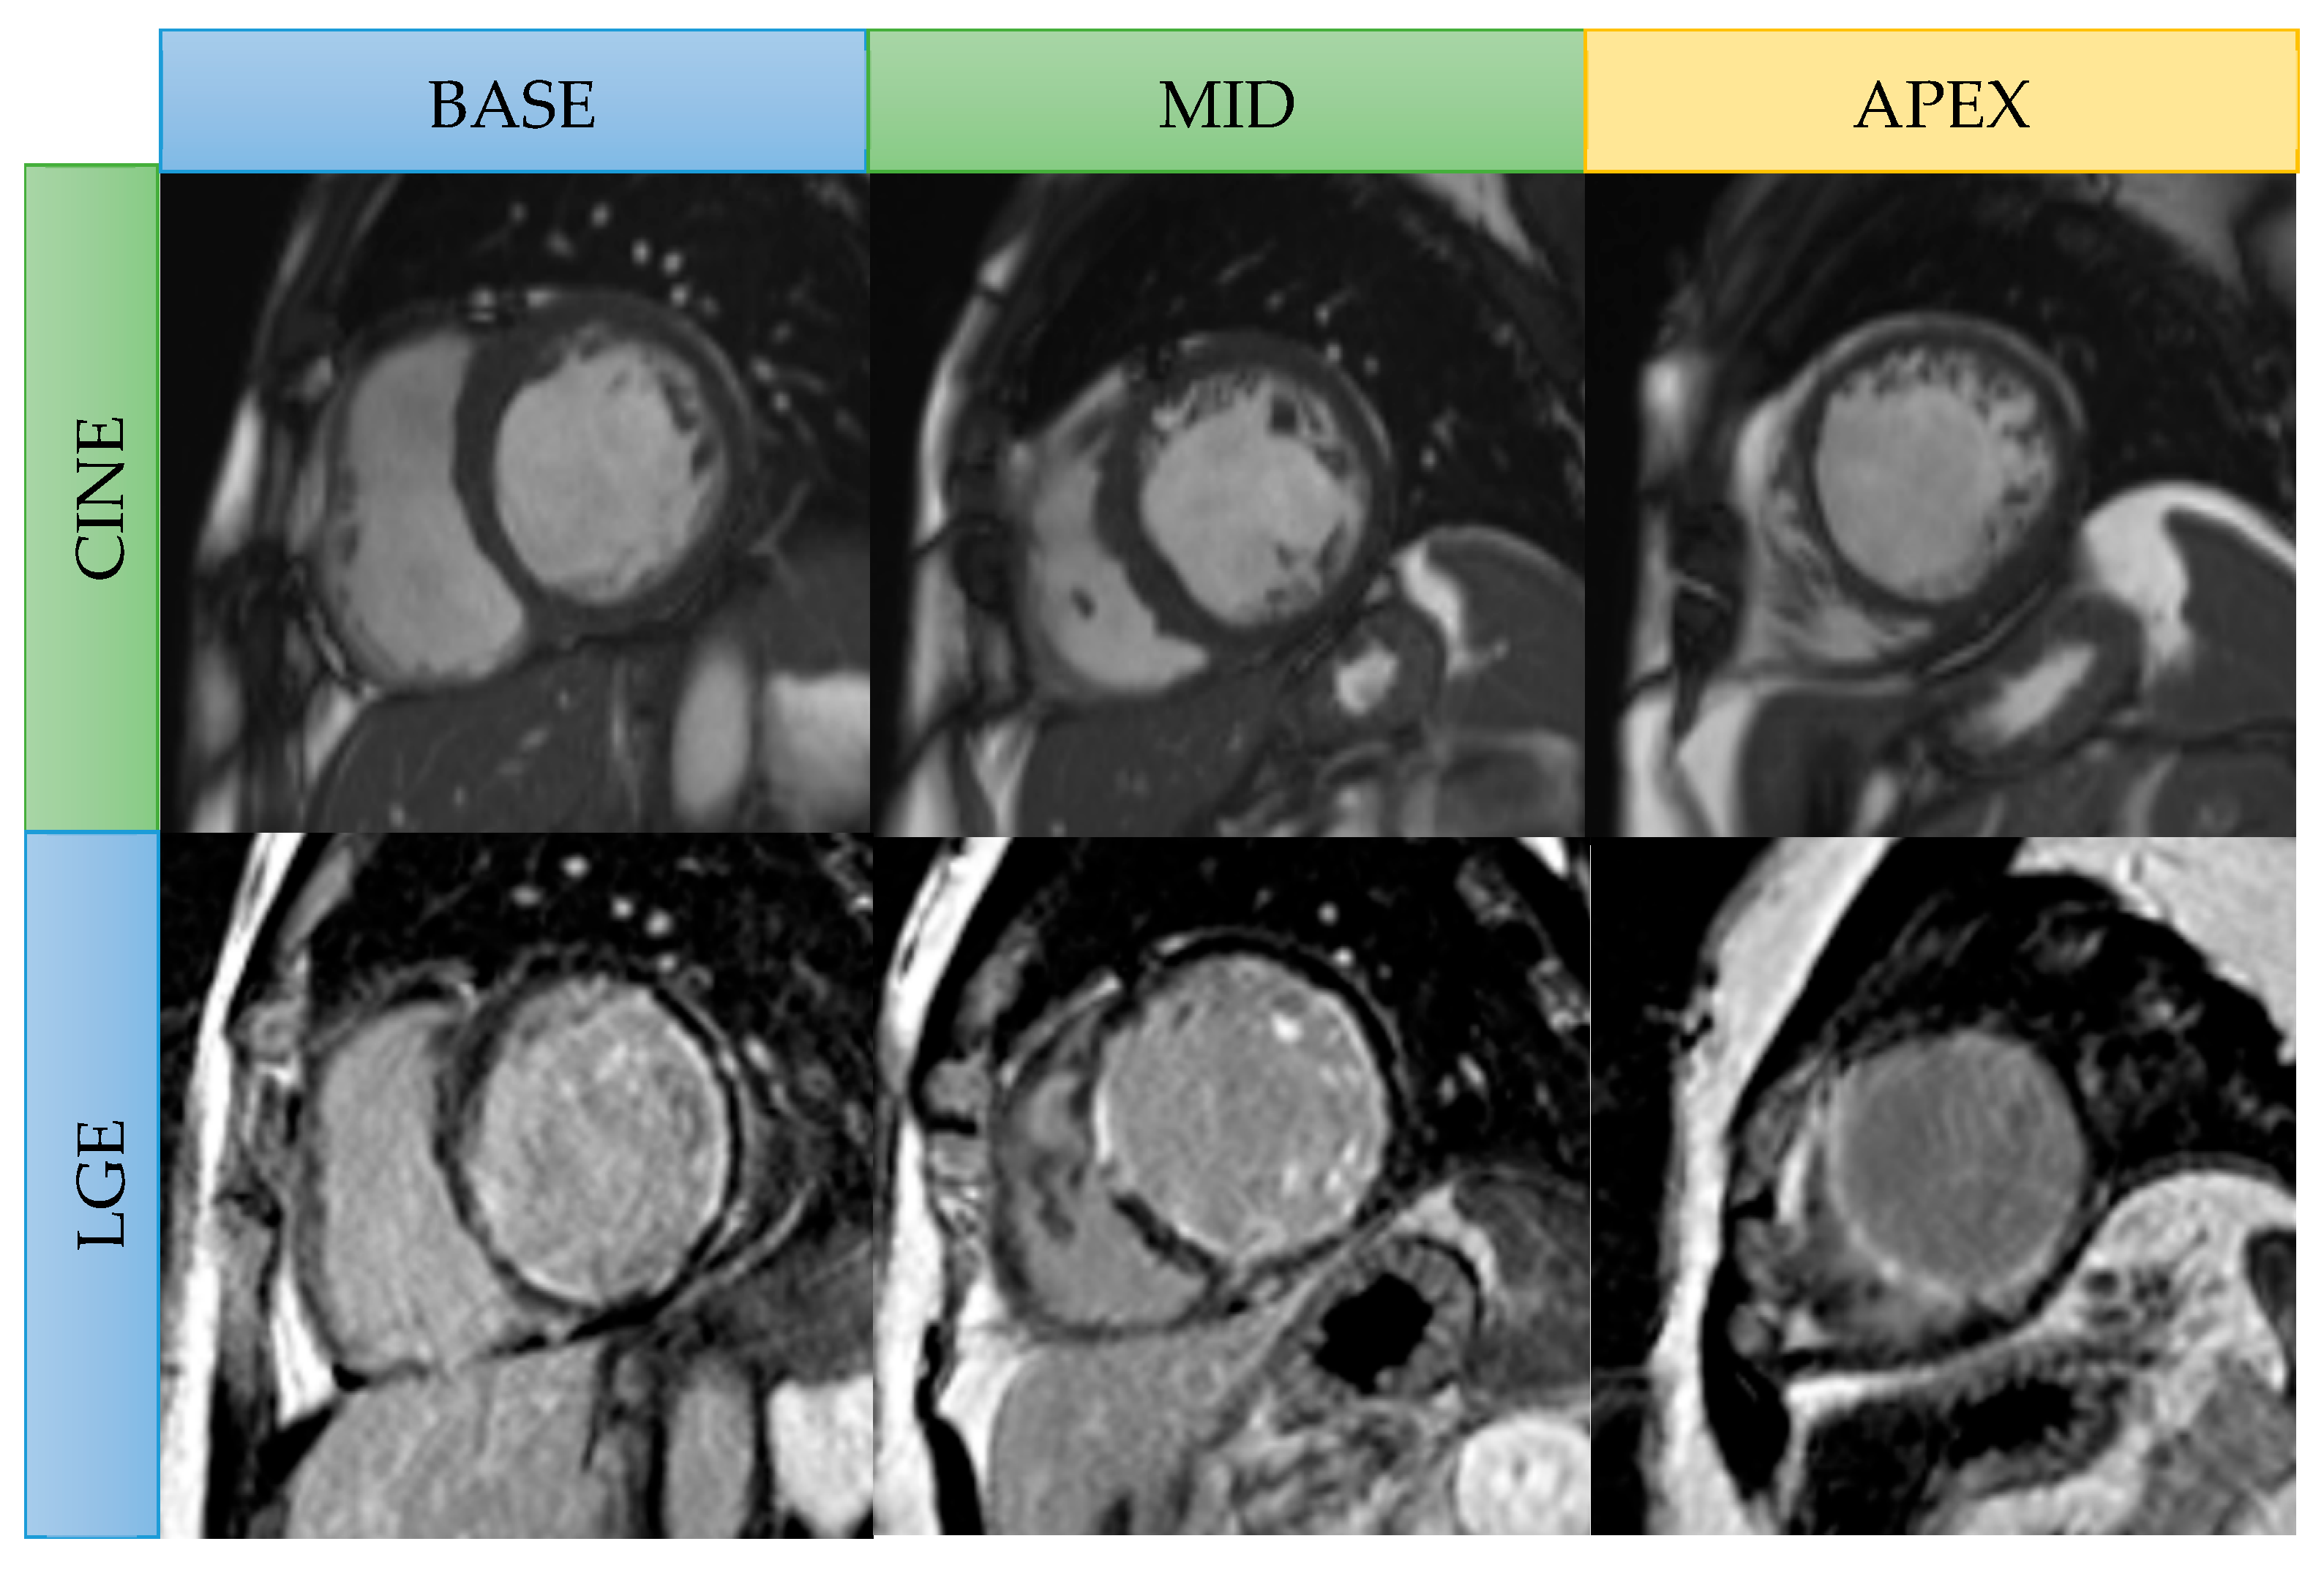

Figure 1.

Stress CMR images in a patient with chronic total occlusion of the mid-right coronary artery. Stress and rest perfusion images: subendocardial areas at the basal to mid inferoseptal and inferior wall in stress images are in keeping with inducible ischemia (arrow). Cine images: no left ventricular wall thinning. Late gadolinium enhancement: focal subendocardial late gadolinium enhancement at the mid inferoseptal wall (arrow).